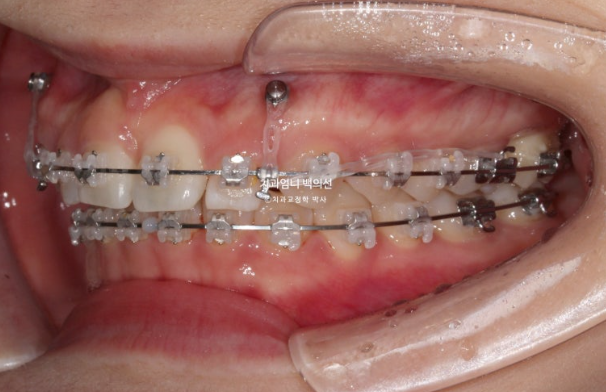

24.02

미니스크류를 사용했고

과개교합 해소를 위해 앞니에 바이트블럭도 붙였습니다.

그렇게 치료를 이어가다가 25년 1월에 치료를 마무리 했습니다.

총 치료기간은 1년 10개월 입니다.